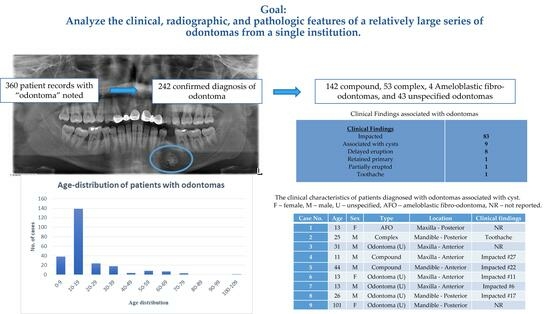

3. Results

3.1. Clinical, Radiographic, and Pathologic Characteristics

| Number of Cases | 242 |

|---|---|

| Gender | |

| Male | 126 |

| Female | 116 |

| Age (Years) | |

| Range | 3–101 |

| Mean | 19.5 |

| Median | 14 |

| Adult/Pediatric | |

| Pediatric (<18 years) | 169 |

| Adult (>18 years) | 73 |

| Type of Dentition | |

| Primary (<6 years) | 2 |

| Mixed (6–13 years) | 118 |

| Permanent (>13 years) | 122 |

| Age Distribution (Years) | |

| 0–9 | 38 |

| 10–19 | 139 |

| 20–29 | 24 |

| 30–39 | 18 |

| 40–49 | 4 |

| 50–59 | 8 |

| 60–69 | 7 |

| 70–79 | 3 |

| 80–89 | 0 |

| 90–99 | 0 |

| 100–109 | 1 |

| Jaw | |

| Maxilla | 117 |

| Mandible | 122 |

| Unspecified | 3 |

| Location | |

| Anterior | 137 |

| Posterior | 95 |

| Unspecified | 10 |

| Type | |

| Compound | 142 |

| Complex | 53 |

| AFO | 4 |

| Unspecified (odontoma) | 43 |

| Pathologic/radiographic confirmation | |

| Pathologic alone | 197 |

| Radiographic alone | 42 |

| Both | 3 |

| Associated Cyst | |

| Dentigerous | 8 |

| Nasopalatine duct cyst | 1 |

| Clinical Findings | |

| Impacted | 83 |

| Delayed eruption | 8 |

| Retained primary | 1 |

| Partially erupted | 1 |

| Toothache | 1 |